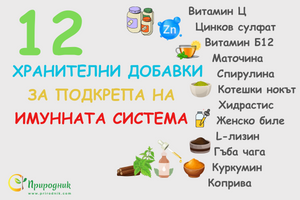

Пет начина да подсилите имунната си система

от Aneliya Dikova • 5 мин. четенеЗаедно с предстоящите зимни месеци, връщането на децата в училище е период, в който те са изправени пред по-големи предизвикателства за имунитета си като цяло. Претъпканите класни стаи и коридори, повишеният социален и академичен стрес и повечето време, прекарано на закрито, в съчетание с често не особено добрите навици за лична хигиена на децата, допринасят за повече възможности за излагане на въздействието на инфекции и за по-неблагоприятна среда за силен имунен отговор. Освен това, когато имунната система на децата е претоварена, това може да се отрази и на останалите членове на семейството! -

Съвети при настинка и грип

от Aneliya Dikova • 15 мин. четенеКога за последен път сте имали симптоми на настинка или грип? Някои хора се заразяват с грипен вирус всяка година или няколко пъти годишно. Независимо дали става въпрос за възпалено гърло, инфекция на синусите, бронхит или пневмония, грипният вирус може да предизвика множество нежелани и дори животозастрашаващи симптоми и състояния. В тази статия ще научите как да си помогнете за предотвратяването на грипа, кои хранителни добавки и храни да включите в диетата си и какви мерки можете да предприемете, за да се излекувате ако сте се разболели от грип. -